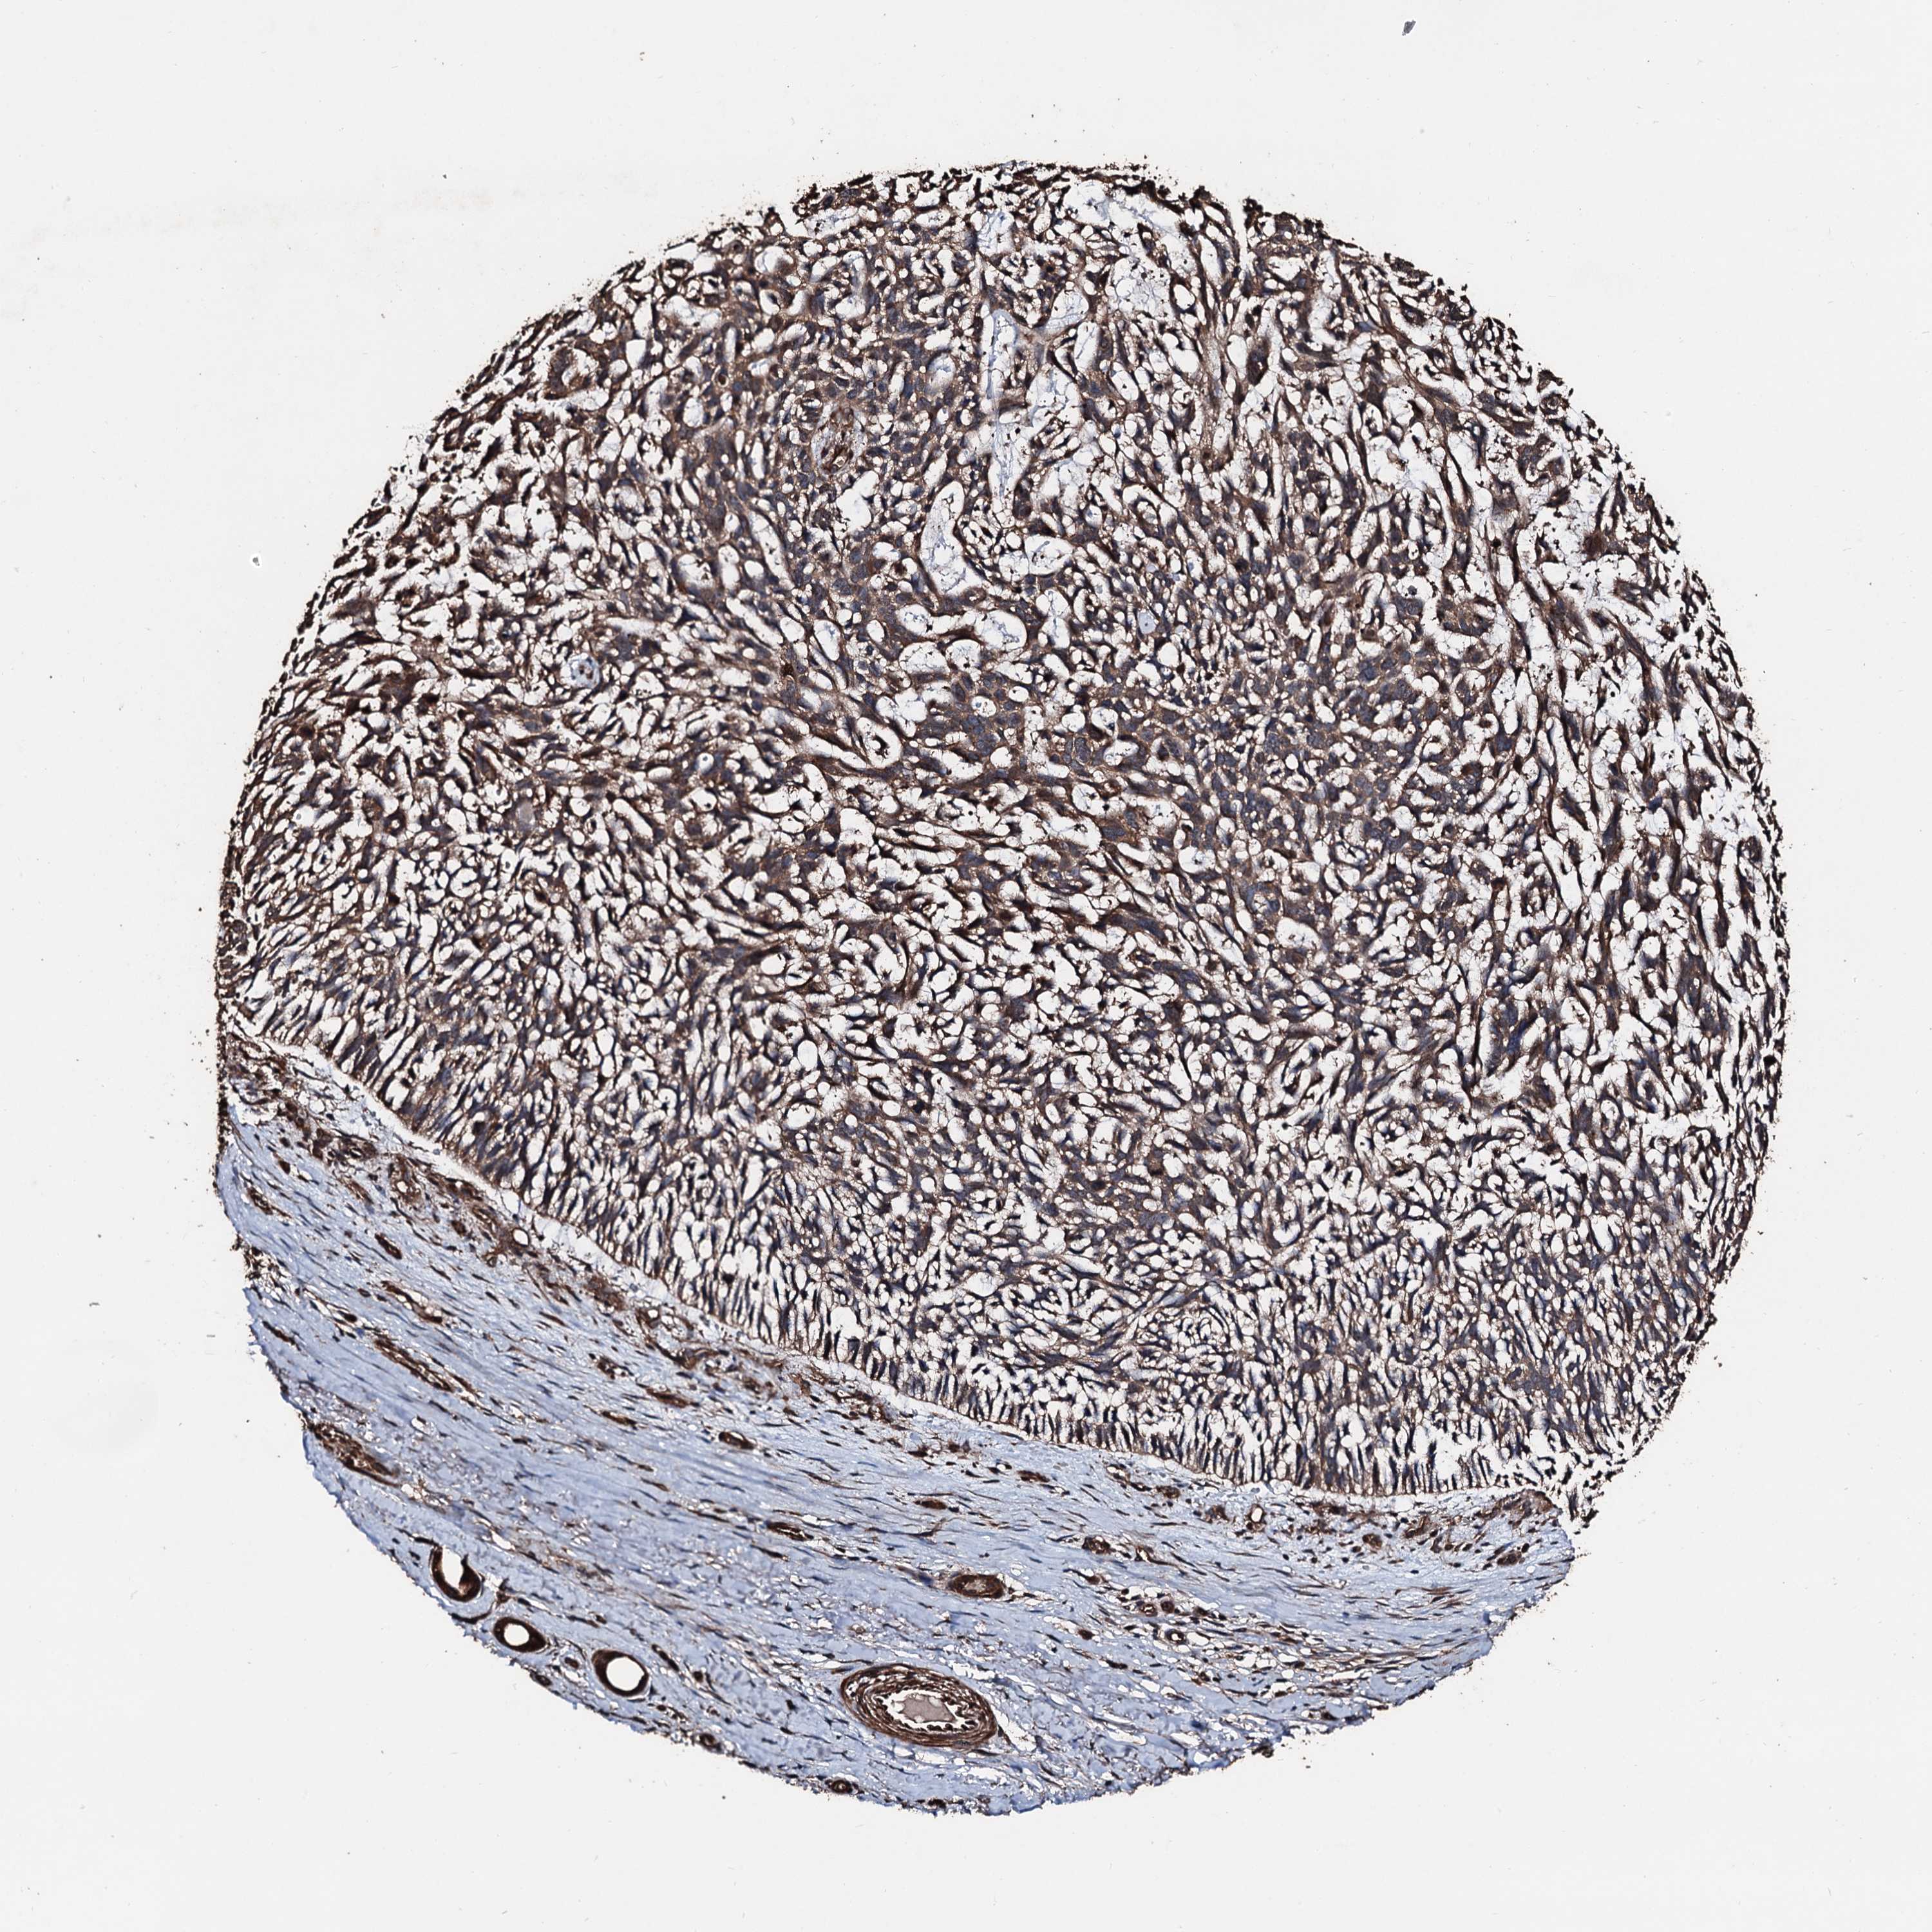

SKIN CANCER - Protein expressioni

A mouse-over function shows sample information and annotation data. Click on an image to view it in a full screen mode. Samples can be filtered based on level of antibody staining by selecting one or several of the following categories: high, medium, low and not detected. The assay and annotation is described here.

Antibody staining in the annotated cell types in the current human tissue is reported as not detected, low, medium, or high, based on conventional immunohistochemistry profiling in selected tissues. This score is based on the combination of the staining intensity and fraction of stained cells.

Each image is clickable and will lead to virtual microscopy that enables deeper exploration of all samples and also displays staining intensity scores, fraction scores and subcellular localization as well as patient and tissue information for each sample.

Antibody HPA039484

Squamous cell carcinoma, NOS